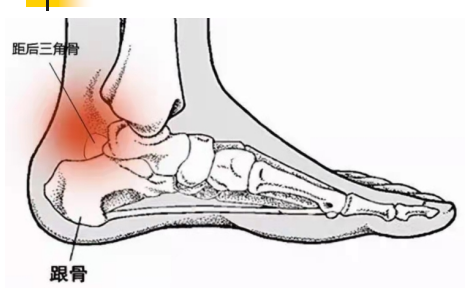

1840年Rosenmuller首先描述了 距后三角骨的存在。

距后三角骨总的发生率在1.7--7%

在青春期前(男性11岁--13岁,女性8--10岁),距骨后内侧结节和后外侧结节出现第二骨化中心,并在一 年内与距骨体融合。

但在足球、体操、武术、舞蹈等运动项目中,因跖屈 动作过多,会导致距后三角骨在胫骨后唇和跟骨之间 反复撞击,从而产生疼痛不适,影响运动,称为“疼痛 性距后三角骨” 。

踝关节后方撞击引起的疼痛性距后三角骨,也有学者 称其为:三角骨综合征。